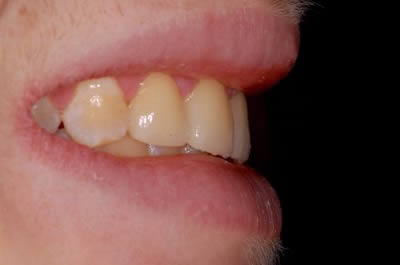

Case Studies

Dental Crowns (7 images)